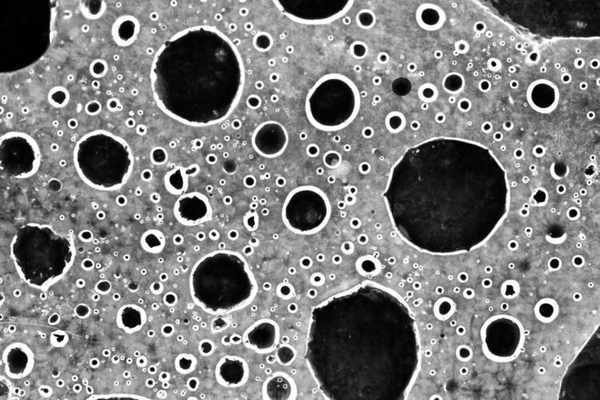

質子治療也稱為質子束療法,是一種先進的治療管道,指的是使用質子加速器,產生高能質子束,再精准地控制攝入患者的體內,釋放到病變的部位,進而起到治療的效果。

該項治療的效果,相對於傳統的放射性治療,更能有效給予腫瘤細胞的根治劑量,並且不會損傷腫瘤以外的正常組織,也是臨床上比較常用的治療管道。

質子治療最理想的效果就是給於腫瘤細胞根治劑量,而不損傷正常細胞。而傳統的放射治療在治療腫瘤的同時,還會不可避免地損傷正常組織,並且腫瘤還無法得到根治性的效果。

對於深入人體部位的實體腫瘤,比如肝臟腫瘤、兒童腦部腫瘤來說,質子治療都能够達到精准治療的效果。要知道正常的放射治療過程中,癌周邊的正常皮膚因射線輻射的原因,也會有誘發癌變的可能。

而質子治療在能更深入精准的治療下,還能够保證癌周圍的正常組織的安全,囙此可以大大降低二次誘發癌症的風險